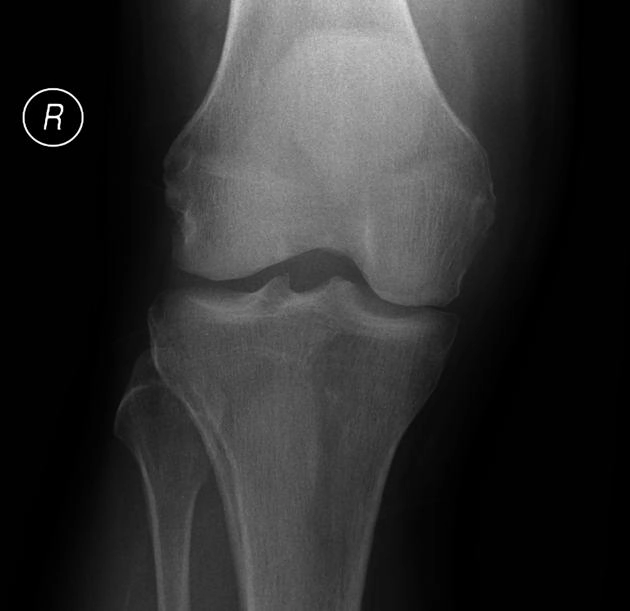

Gãy mâm chày (Tibial Plateau Fracture)

16/03/2026